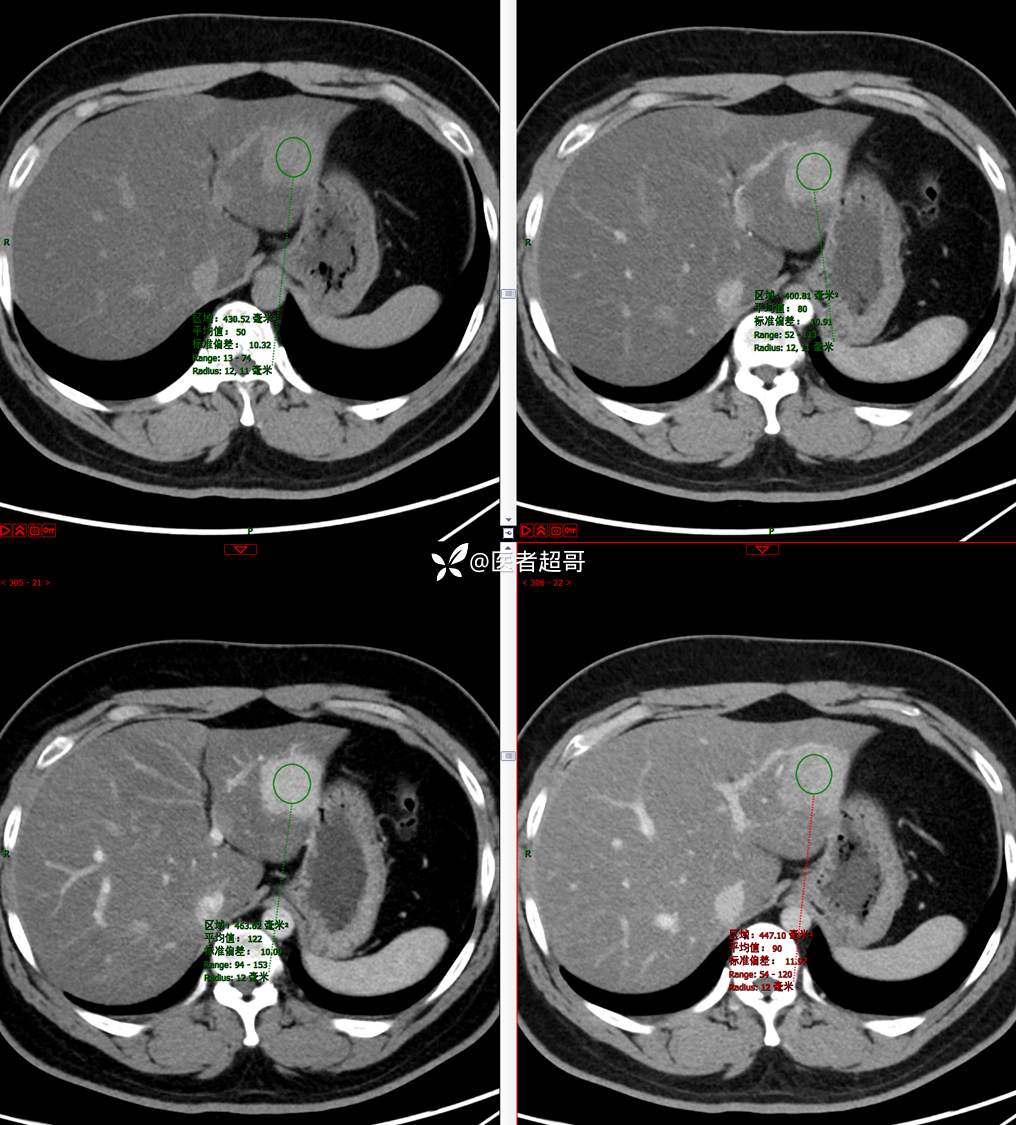

【影诊笔记685】男,31y,发现肝占位性病变5天就诊,请诊断分析,有病理结果!

主 诉:发现肝占位性病变5天。

现病史:患者缘于5天前体检时发现肝占位性病变,未予以特殊处置。现患者为求系统诊治就诊于我院,行普美显提示:肝左叶富血供占位,请结合临床及其他检查,肝多发血管瘤,脂肪肝,肝囊肿,请结合临床。门诊以“肝占位性病变”收入我科。病程中,饮食睡眠可,二便可,近期体重未见明显变化。